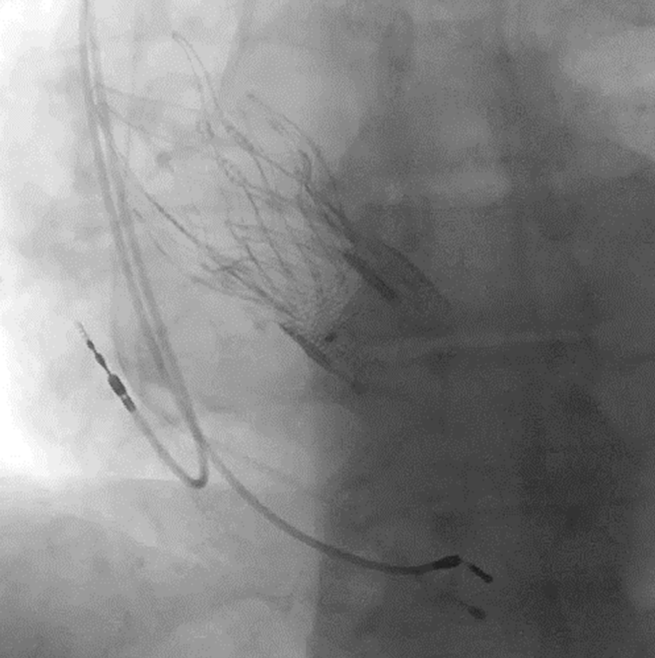

Операция выполнялась руководителем Отдела рентгенэндоваскулярных методов диагностики и лечения, главным научным сотрудником, д.м.н. Меркуловым Е.В., старшим научным сотрудником, к.м.н. Терещенко А.С. и научным сотрудником, к.м.н. Арутюнян Г.К. Клиническую подготовку и анестезиологическую поддержку обеспечивали сотрудники Отдела неотложной кардиологии (руководитель отдела - главный научный сотрудник, д.м.н. Певзнер Д.В.), а также сотрудники блока интенсивного наблюдения под руководством заведующего Зюряева И.Т. и врачей Кушнира П.Ф., Дулаева Л.О., Тереничевой М.А. Во время вмешательства осуществлялся ангиографический контроль проходимости коронарных артерий с раздуванием баллона в корне аорты. Эндоваскулярное вмешательство прошло без осложнений с хорошим клиническим результатом. У пациента полностью регрессировала недостаточность аортального клапана. Пациент с улучшением состояния был выписан из Отдела неотложной кардиологии НМИЦ кардиологии им. ак. Е.И. Чазова Минздрава России. За ним будет продолжено динамическое клиническое наблюдение.

Результат вмешательства